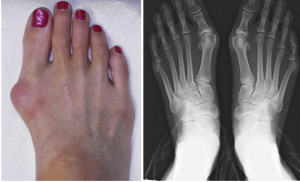

Lek protiv čukljeva gotovo da i ne postoji. Međutim, predstavljmo vam prirodni lek kojim ćete provereno ublažiti bolove koje izazivaju čukljevi.